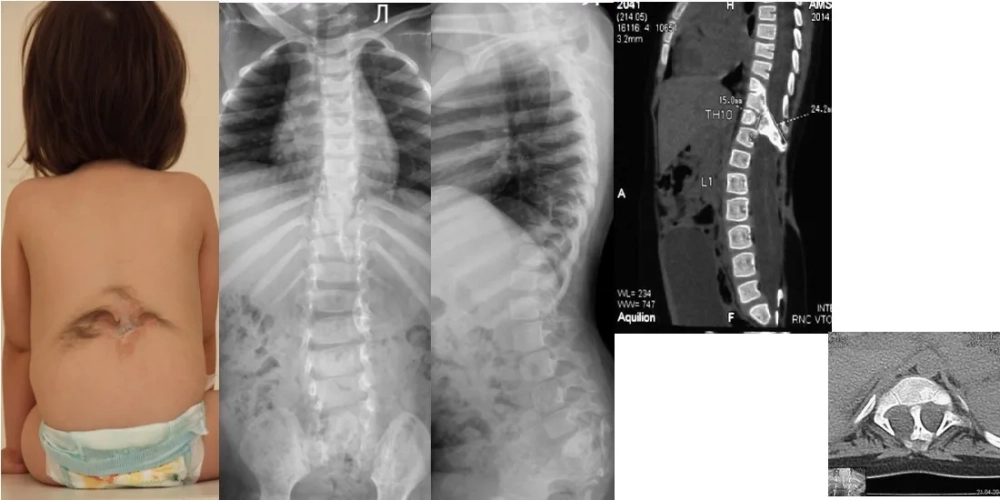

• The most severe form, myelomeningocele, involves a sac of fluid protruding from the back, containing part of the spinal cord and nerves.

A baby who has had spina bifida surgery